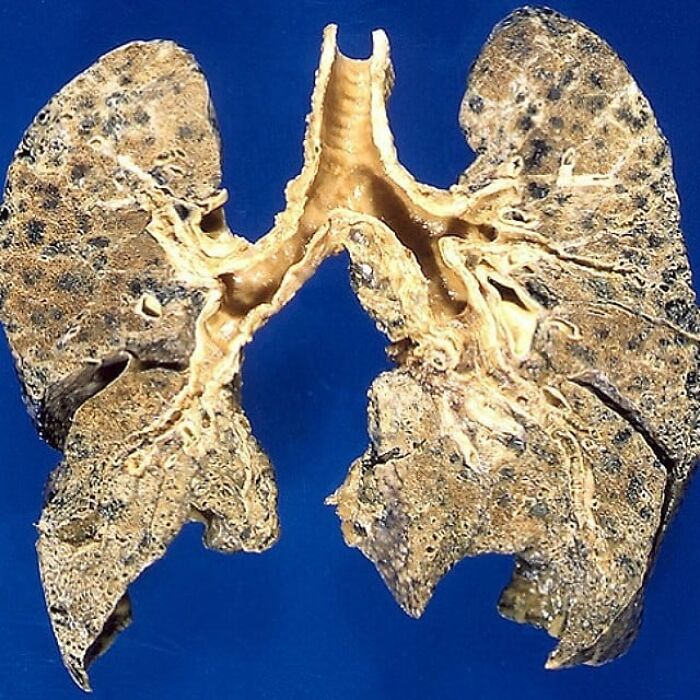

Cross Section Of The Lungs Of A Patient With Copd (Emphysema , Chronic Bronchitis And Asthma)